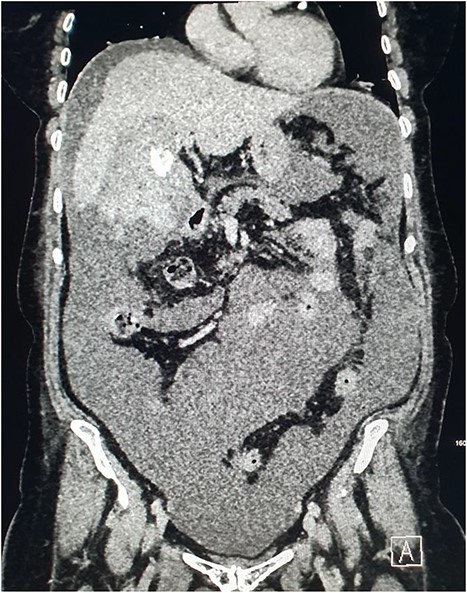

CT of the abdomen was performed the following week due to pyrexia and ongoing pain. This demonstrated abscess formation at the site of haematoma in the gallbladder fossa (Fig. 6). A locking pigtail drain was placed in the gallbladder fossa collection under ultrasound guidance. Slow drainage of bloodstained bilious fluid from the right upper quadrant with resolution was demonstrated on CT the following month (Fig. 7). The patient was discharged with gallbladder (GB) fossa drain and biliary stent in situ to await elective cholecystectomy.

CT demonstrating superinfection of the gallbladder fossa haematoma and abscess formation.

Radiographic and CT images demonstrating the patients’ hardware at discharge with an endoscopic biliary stent and gallbladder fossa pigtail drain in situ.